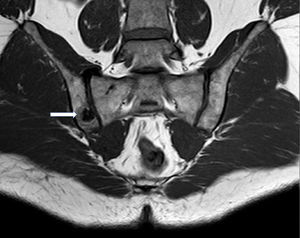

El paciente refería dolor en nalga derecha, que le despertaba por la noche, mejorando con antiinflamatorios no esteroideos (AINE). No había presentado ningún antecedente traumático, fiebre, artritis ni en la anamnesis aparecían datos relacionados con espondiloartritis o infecciones recientes. La exploración física era completamente normal, siendo las maniobras de sacroilíacas negativas (Fabere, apertura, cierre y Laguerre), y no presentando limitación funcional articular periférica ni axial. La exploración neurológica no reveló ningún dato patológico. La analítica realizada no presentaba alteraciones, con normalidad en los reactantes de fase aguda. En cuanto a las técnicas de imagen, en la radiografía simple de pelvis no se objetivaron alteraciones óseas evidentes, por lo que se solicitó resonancia magnética nuclear (RMN) de sacroilíacas, apreciándose área hipointensa en secuencia T1 (fig. 1) e hiperintensa en STIR (fig. 2) en borde ilíaco de sacroilíaca derecha, con zona central isointensa en T1 (fig. 1) e hipointensa en STIR (fig. 2), orientando hacia el diagnóstico definitivo de osteoma osteoide, que se confirmó mediante tomografía computarizada (TC). El paciente se trató mediante ablación por radiofrecuencia guiada por TC quedando asintomático.